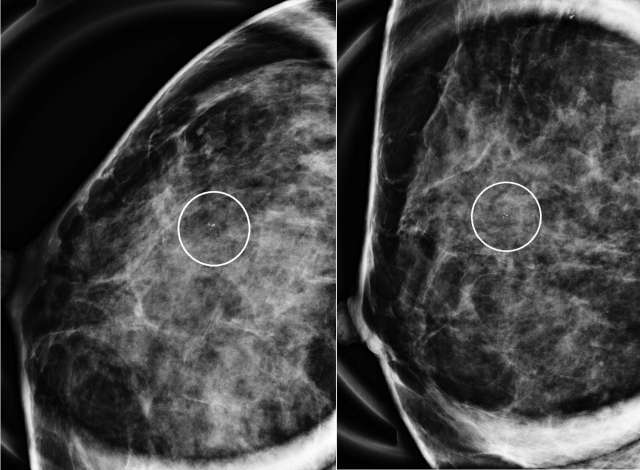

The mammographic appearance of ADH is usually that of grouped or regional calcifications, most often of the amorphous or coarse heterogeneous subtype. ADH can also be less commonly present as a mass or focal asymmetry on screening mammograms. As calcifications are the most common presentation of ADH on screening mammograms, and as ultrasound suboptimally evaluates areas of calcification, ADH is less often seen on ultrasound examinations. However, the most common sonographic feature of lesions demonstrating ADH on ultrasound-guided biopsies includes a hypoechoic, microlobulated mass without acoustic transmission or shadowing. The most common appearance of ADH on breast MRI is nonmass enhancement in a focal, linear, segmental, or regional distribution. The second-most common appearance is that of an enhancing mass.